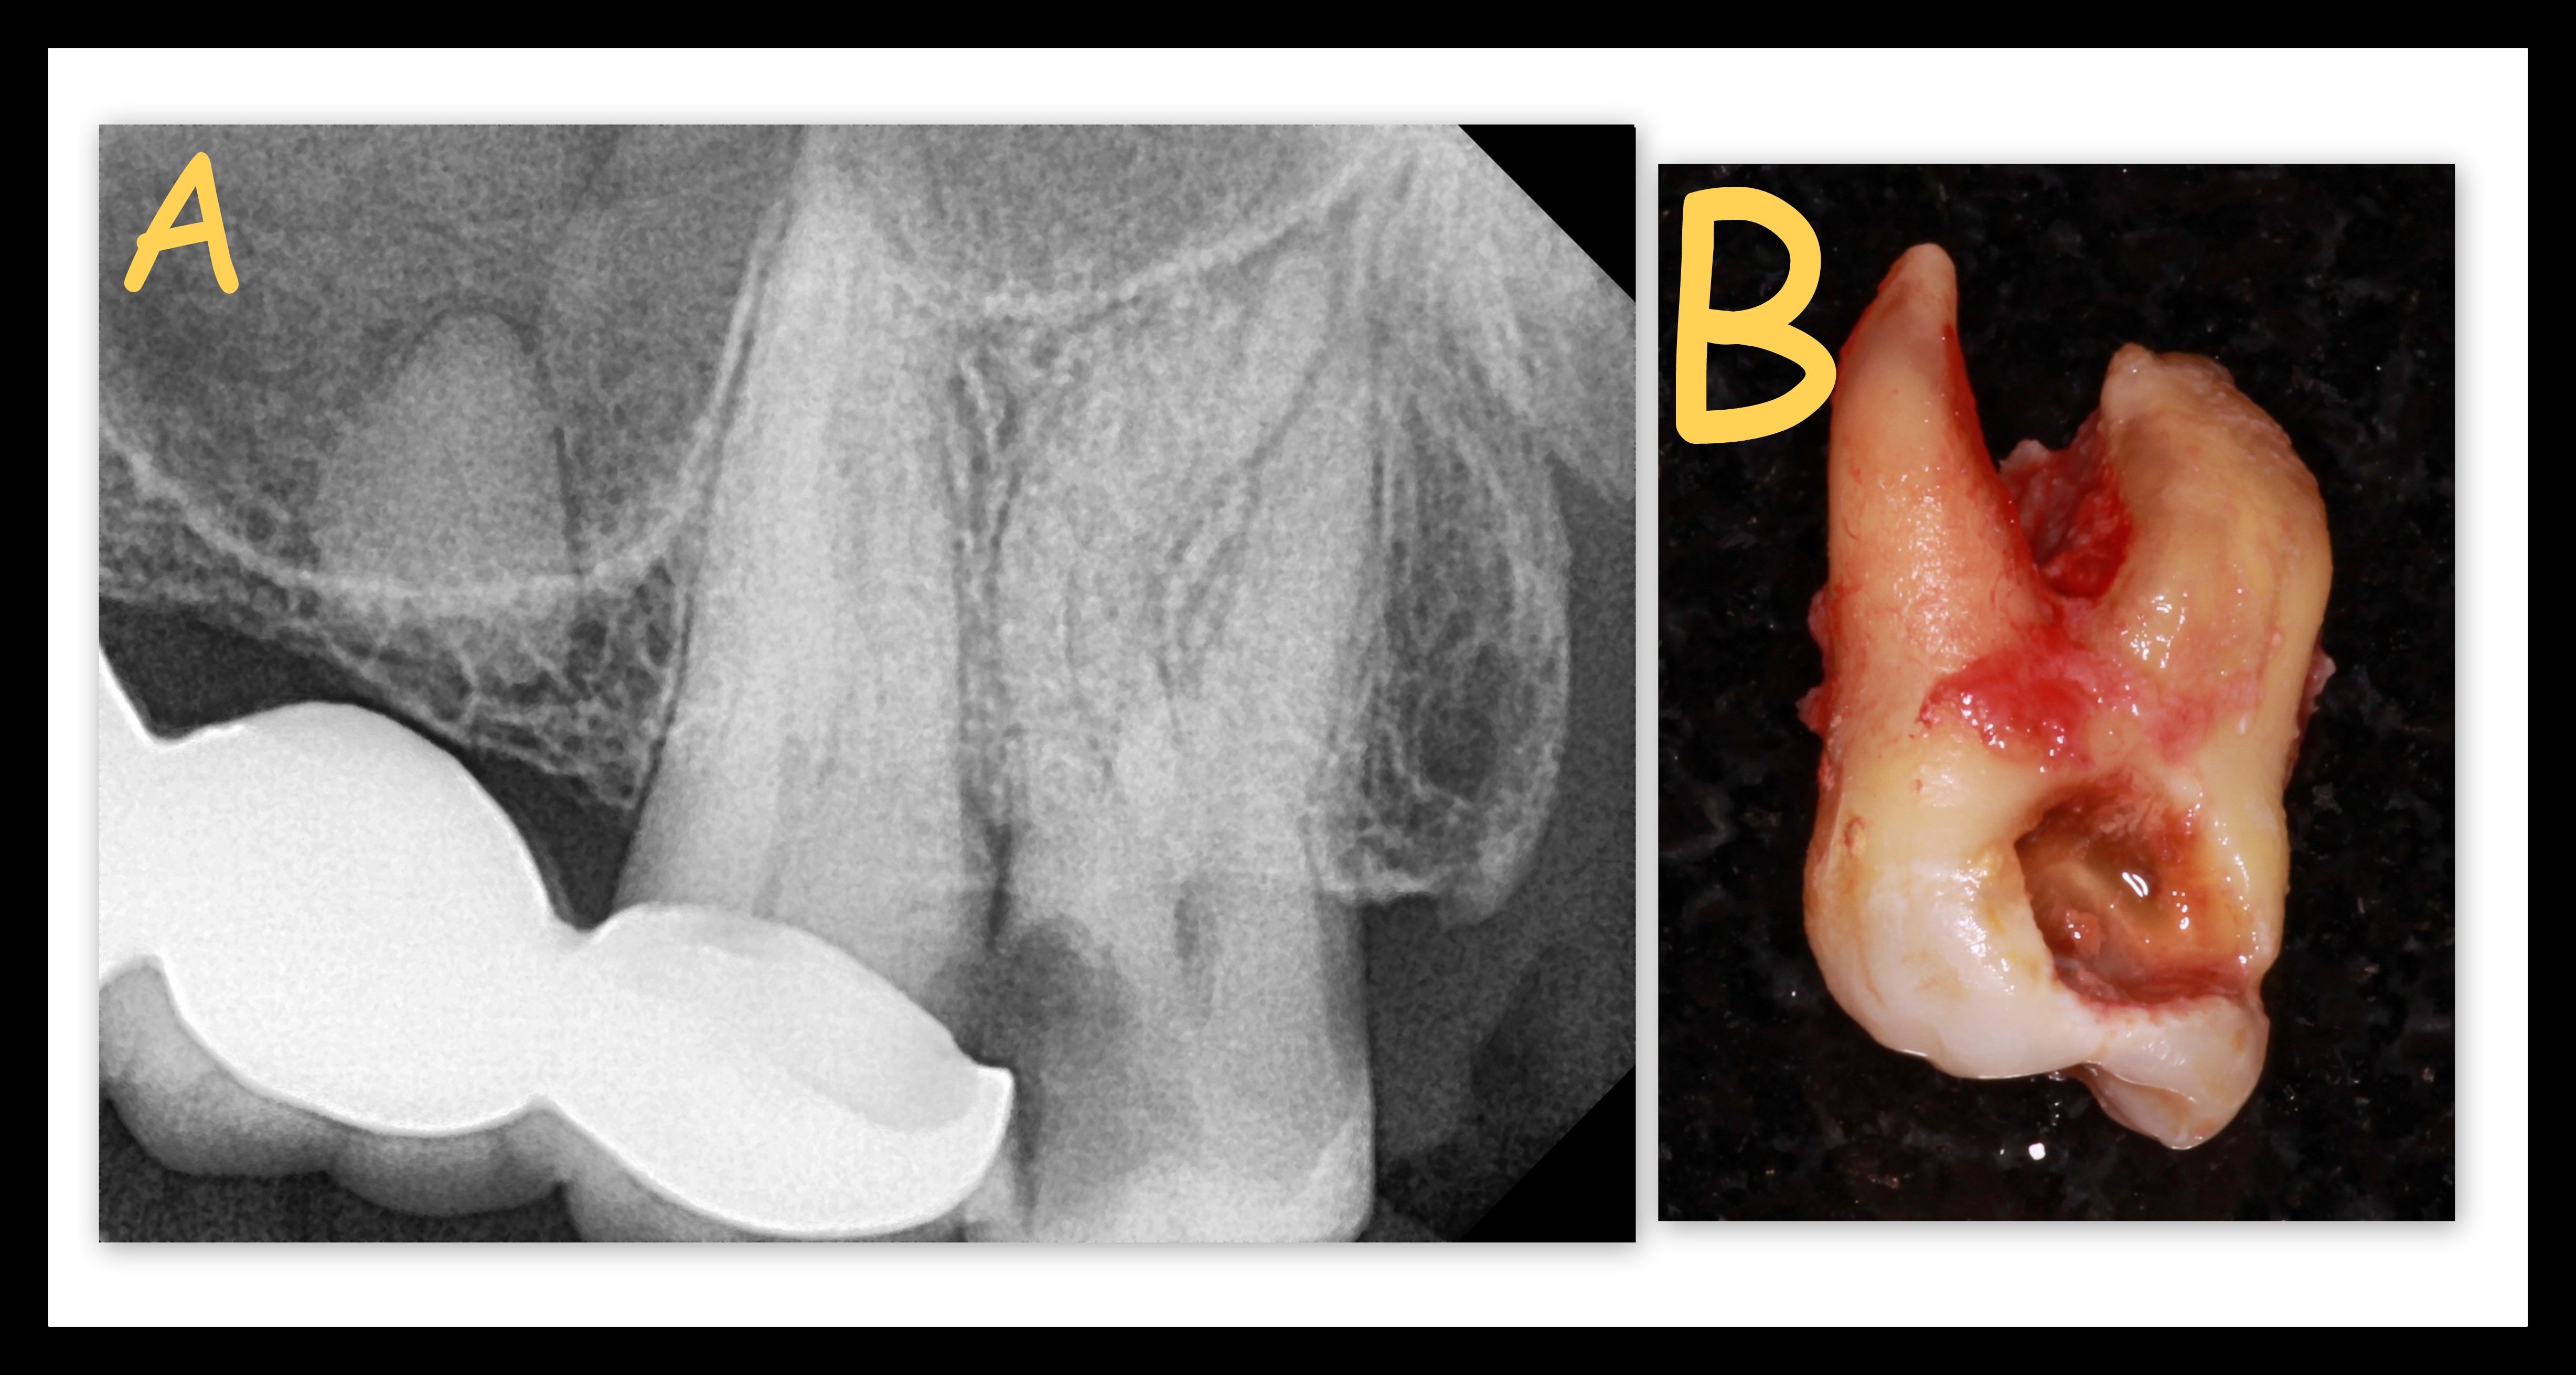

Wisdom tooth extraction is recommended in cases of decayed, un-erupted or wrongly erupting last molar teeth. Symptoms of the above may be pain while opening their mouth or chewing food, severe or dull nagging tooth ache, ear/jaw pain, difficulty in eating due to swelling of gums around the tooth.

- Tilted or wrongly erupting wisdom teeth are very difficult to clean and will most definitely get decayed if extraction is prolonged.

- Decay will spread to neighbouring teeth leading to cavities or even root canal.